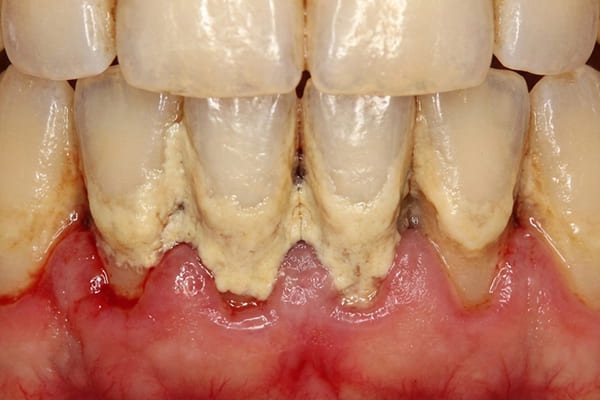

中度歯周炎 危険度★★★

中程度の歯周炎になると、口臭がおこり、歯茎が化膿します。ブラッシングをした際に膿がでることもあります。

歯周ポケットは4~5mm程度です。

この段階での治療法はスケーリングなどを使用して治療をしますが、歯周ポケットが5

mm以上深くなるとフラップ手術をする場合があります。フラップ手術は局所麻酔後、歯茎を切開し、隠れているプラークや歯石を取り除き、歯周病の進行を止める手術を行うことがあります。